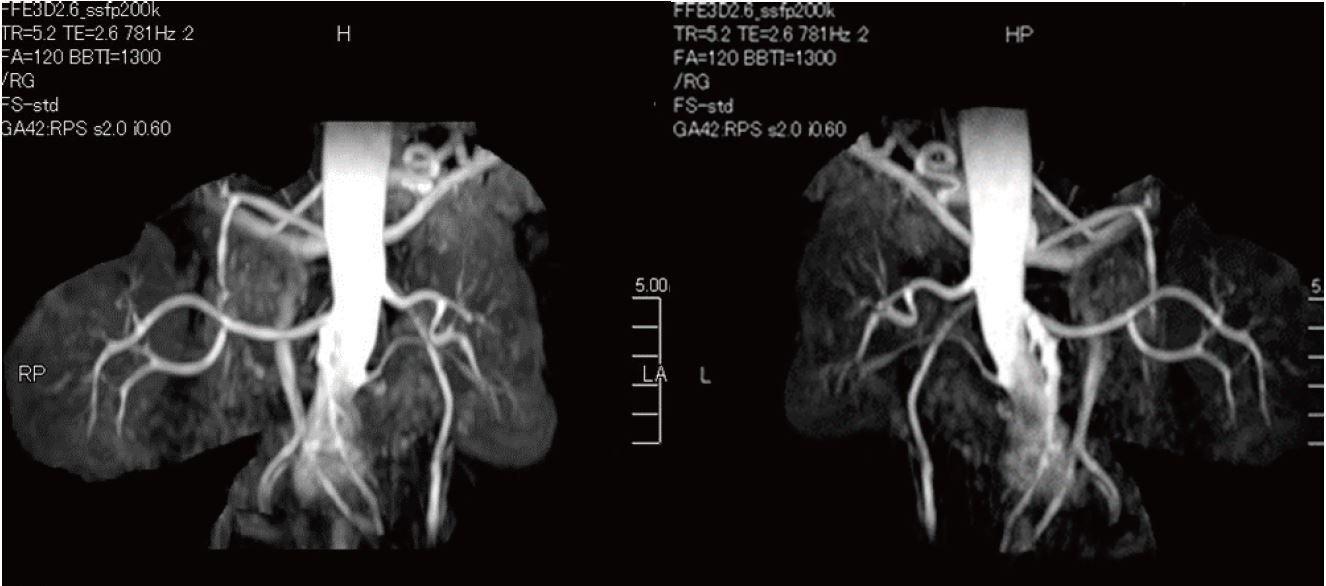

Ангіо-МРТ з використанням методу Time-SLIP

46-річна людина, гіпертонік, ангіо-МРТ з використанням методу Time-SLIP

Метод Time-SLIP

Техніка з використанням парамагнитного контрасту